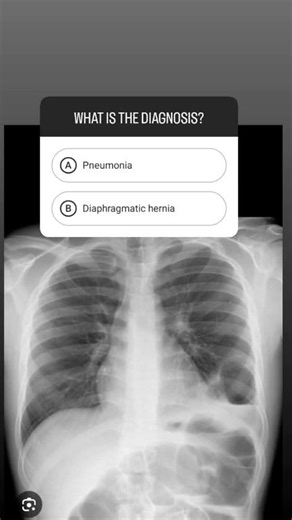

Diagnosis ✅ comments follow me ✅ #drmhmedical #knowledge #do